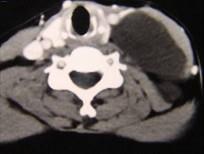

问题 男性,40岁,颈部出现无痛性囊性包块2年余,CT扫描如图所示,最可能诊断为()

选项 A.淋巴管瘤 B.血管瘤 C.淋巴结肿大 D.神经源性肿瘤 E.颈动脉鞘瘤

答案 A